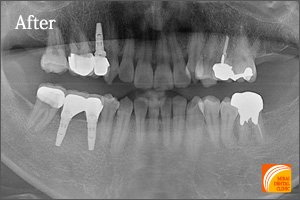

After

左下奥3本を失われた患者さんです。3本歯がないからといって3本インプラントが必要なわけではありません。2本インプラントを埋入することにより3本の歯を支えるインプラントブリッジにより治療しました。